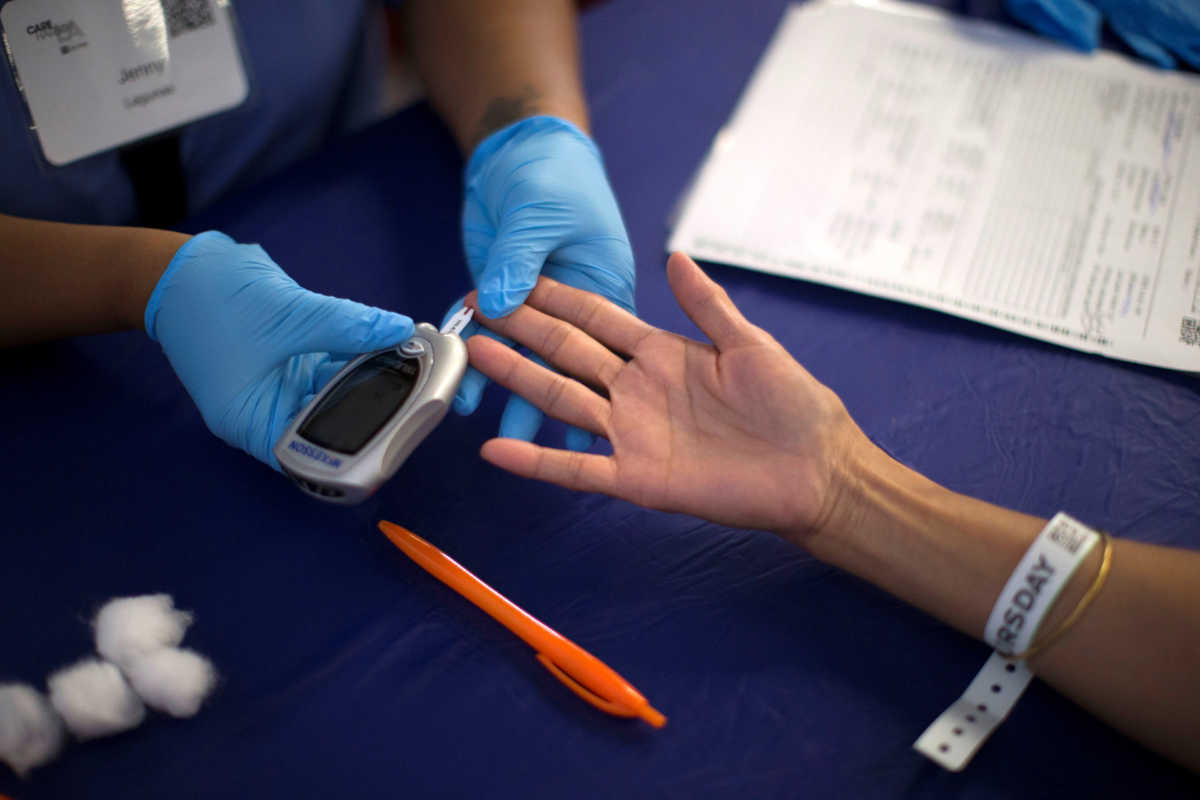

Διευκρινίσεις για τα αναλώσιμα του Σακχαρώδους Διαβήτη τύπου Ι δίνει το υπουργείο Υγείας, τονίζοντας ότι για πρώτη φορά στη χώρα μας...